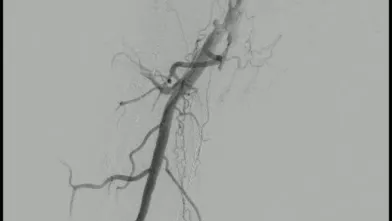

過去にSFAに留置された総長約35 cmの3本のBMSの入口部からの閉塞(動画1)近位端はSFA入口部から1 cm程度の健常部があり、遠位端は膝窩動脈近位部(P1)で側副血行流入部まで1 cmの余白がある。対側山越えアプローチで6 Frガイディングシースを挿入して治療を開始した。ステント外を通過しないように0.035 inchのガイドワイヤーを選択すると容易に遠位部へ到達することが出来た(動画2)。この手ごたえから血栓性病変であることが予想された。持続吸引カテーテルを用いて何度か血栓吸引を行ったが血流は再開しなかった(動画3)。

血管内超音波(IVUS)を行うとガイドワイヤーはステントの中心部を通過していたが、予想通り病変内には大量の血栓が堆積していた(動画4)。7 mmのバルーンで拡張したのち、ステント遠位端より2 cm程度離れた遠位の健常部にhealthy landingをとって(動画5)バイアバーン® ステントグラフト6 × 250 mmを留置した。近位側はステント近位端より1 cm程度離れたSFA入口部の健常部にhealthy landingをとって(動画6)バイアバーン® ステントグラフト7 × 150 mmを留置した。上下端とも既存のステントより外側にランディングをとること、ステントグラフトの電子添文の「使用上の注意」にあたる主要な側枝に注意して、大腿深動脈(DFA)や側副血行の流入部にかからないよう留意した。後拡張は血栓の上下方向へのprotrusionを防ぐ目的で先に遠位端、近位端の順に高圧バルーンで拡張し健常部血管壁への圧着をとった。ステントグラフトの中間部への後拡張はそのあとに続いて行った。最終造影で末梢まで塞栓がないことを確認して終了した(動画7)。